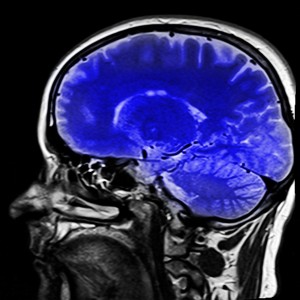

Gehirn: neues Nasenspray gegen Anfälle sehr gut wirksam (Foto: pixabay.com, kalhh) |